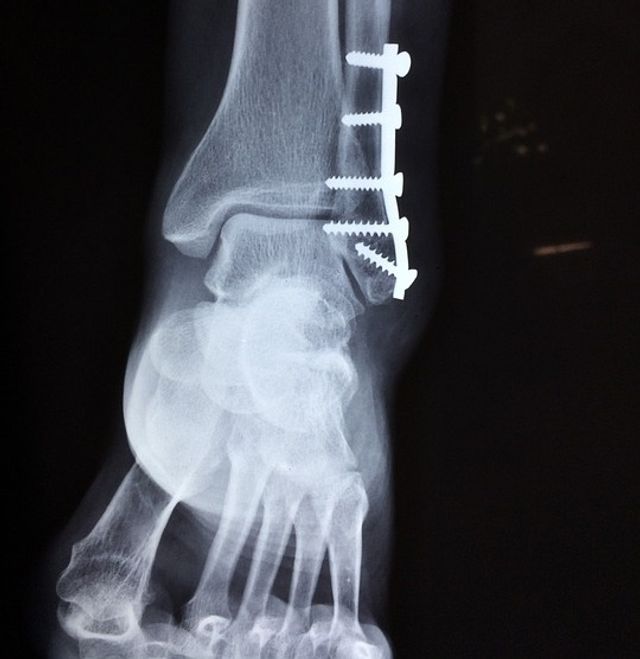

Выяснилось, что весной, когда был гололед, трехлетний мальчик вышел вместе с родителями из больницы и упал. В результате ребенок получил перелом костей правой голени со смещением. Инцидент произошел ввиду халатности сотрудников учреждения: опасный участок тротуара не был посыпан песком.